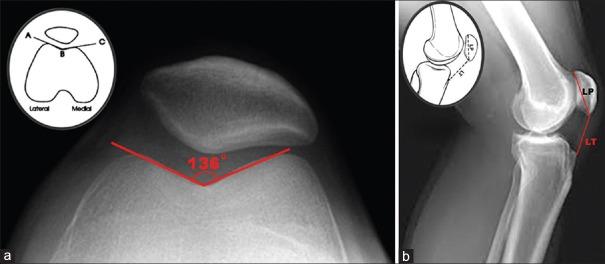

The medial patellofemoral ligament (MPFL) is the primary stabilizer of the patellofemoral joint; its reconstruction has been recommended in adults over the past decade after recurrent patellar instability. However, there has been no standardized technique for reconstruction, therefore, ideal graft and technique for reconstruction are yet undetermined. However, dynamic MPFL reconstruction studies claim to be superior to other procedures as it is more anatomical. This preliminary study aims at assessing the outcomes of MPFL reconstruction in a dynamic pattern using hamstring graft. We performed this procedure in four consecutive patients with chronic patellar instability following trauma. MPFL reconstruction was done with hamstring tendons detached distally and secured to patellar periosteum after being passed through a bony tunnel in the patella without an implant and using the medial collateral ligament as a pulley. In all 4 knees, the MPFL reconstruction was isolated and was not associated with any other realignment procedures. No recurrent episodes of dislocation or subluxation were reported at 24 months followup.

髌股内侧韧带(MPFL)是髌股关节的主要稳定结构;在过去十年中,对于复发性髌骨不稳的成年人,建议进行该韧带重建。然而,目前尚无标准化的重建技术,因此,理想的移植物和重建技术仍未确定。不过,动态MPFL重建研究称其比其他手术更具优势,因为它更符合解剖结构。这项初步研究旨在评估使用腘绳肌移植物进行动态模式下MPFL重建的效果。我们对4例创伤后慢性髌骨不稳的连续患者实施了该手术。MPFL重建采用腘绳肌腱,将其远端离断,穿过髌骨上的骨隧道后固定于髌周骨膜,不使用植入物,并以内侧副韧带作为滑车。在所有4个膝关节中,MPFL重建均为单独进行,未与任何其他对线手术联合。在24个月的随访中,未报告脱位或半脱位的复发情况。